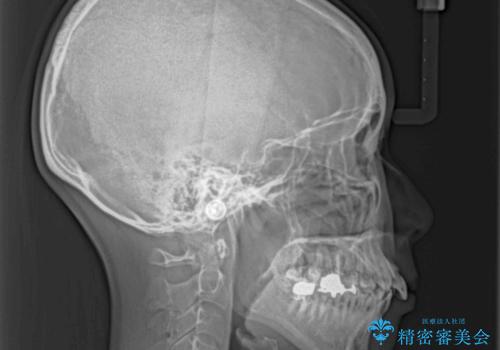

上下の咬み合わせは上顎歯列全体が歯1本分前にずれている状態であり、さらに上顎歯列はV字型に尖っていたため、上下前歯は全く接触していない状態でした。

上顎左右第一小臼歯を抜去して、ワイヤー装置にて口元の突出感を改善するよう矯正治療を行うこととしました。

上顎前歯の歯軸が顕著に改善され、非常に口の閉じやすい歯列に仕上げることができました。